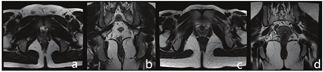

(5)肛管直肠角(anorectal angle,ARA):正中矢状位T2WI图像上直肠后壁与肛管轴线的夹角(图2a、图2b、图2e、图2f)。

a~d:男性,28岁,静态ARA约103.58°,LPA约30.28°,动态最大力排相ARA增加至约111.35°,LPA增加至约55.35° e~h:女性,26岁,静态ARA约92.55°,LPA约22.21°,动态最大力排相ARA增加至约107.38°,LPA增加至约52.61°。

a-d: Male, 28 years old, static ARA was about 103.58°, LPA was about 30.28°, dynamic maximum force phase ARA increased to about 111.35 °, LPA increased to about 55.35 °; e-h: Female, 26 years old, static ARA was about 92.55 °, LPA was about 22.21 °, dynamic maximum force phase ARA increased to about 107.38 °, LPA increased to about 52.61 °.

(6)肛提肌板角(levator plate angle,LPA):正中矢状位T2WI图像上肛提肌板与水平线的夹角(图2c、图2d、图2g、图2h)。